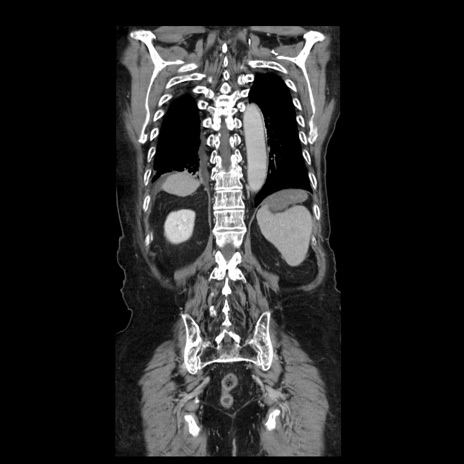

横断像

【症例】70歳代男性

【主訴】腹痛

【現病歴】肝硬変・肝細胞癌にてかかりつけの方。約9時間前に食後より腹痛出現。症状が徐々に増悪し、嘔吐出現したため来院。

【既往歴】肝硬変、肝細胞癌(RFA、TACE後)

【身体所見】意識清明、表情苦悶様、BT 36℃、BP 129/78mmHg、P 88bpm、SpO2 97%(RA)、右上腹部から心窩部にかけて圧痛あり、反跳痛なし、筋性防御あり。

【データ】WBC 5800、CRP 0.16